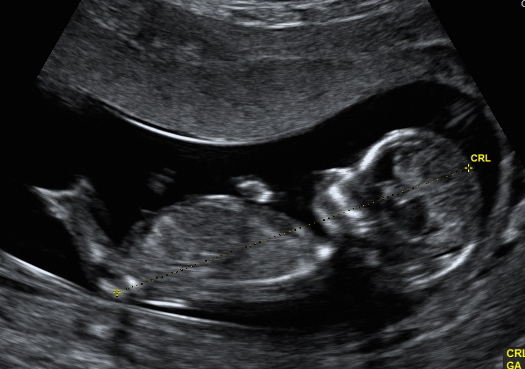

Hi, we have decided not to find out gender but i wanted to know what you ladies thought for a bit of fun while we wait! I'm not too sure if i can even see a nub in the profile but I thought someone here might be able too, also added the potty shot too, again i have no idea if you can see anything! Attachment 33070Attachment 33071